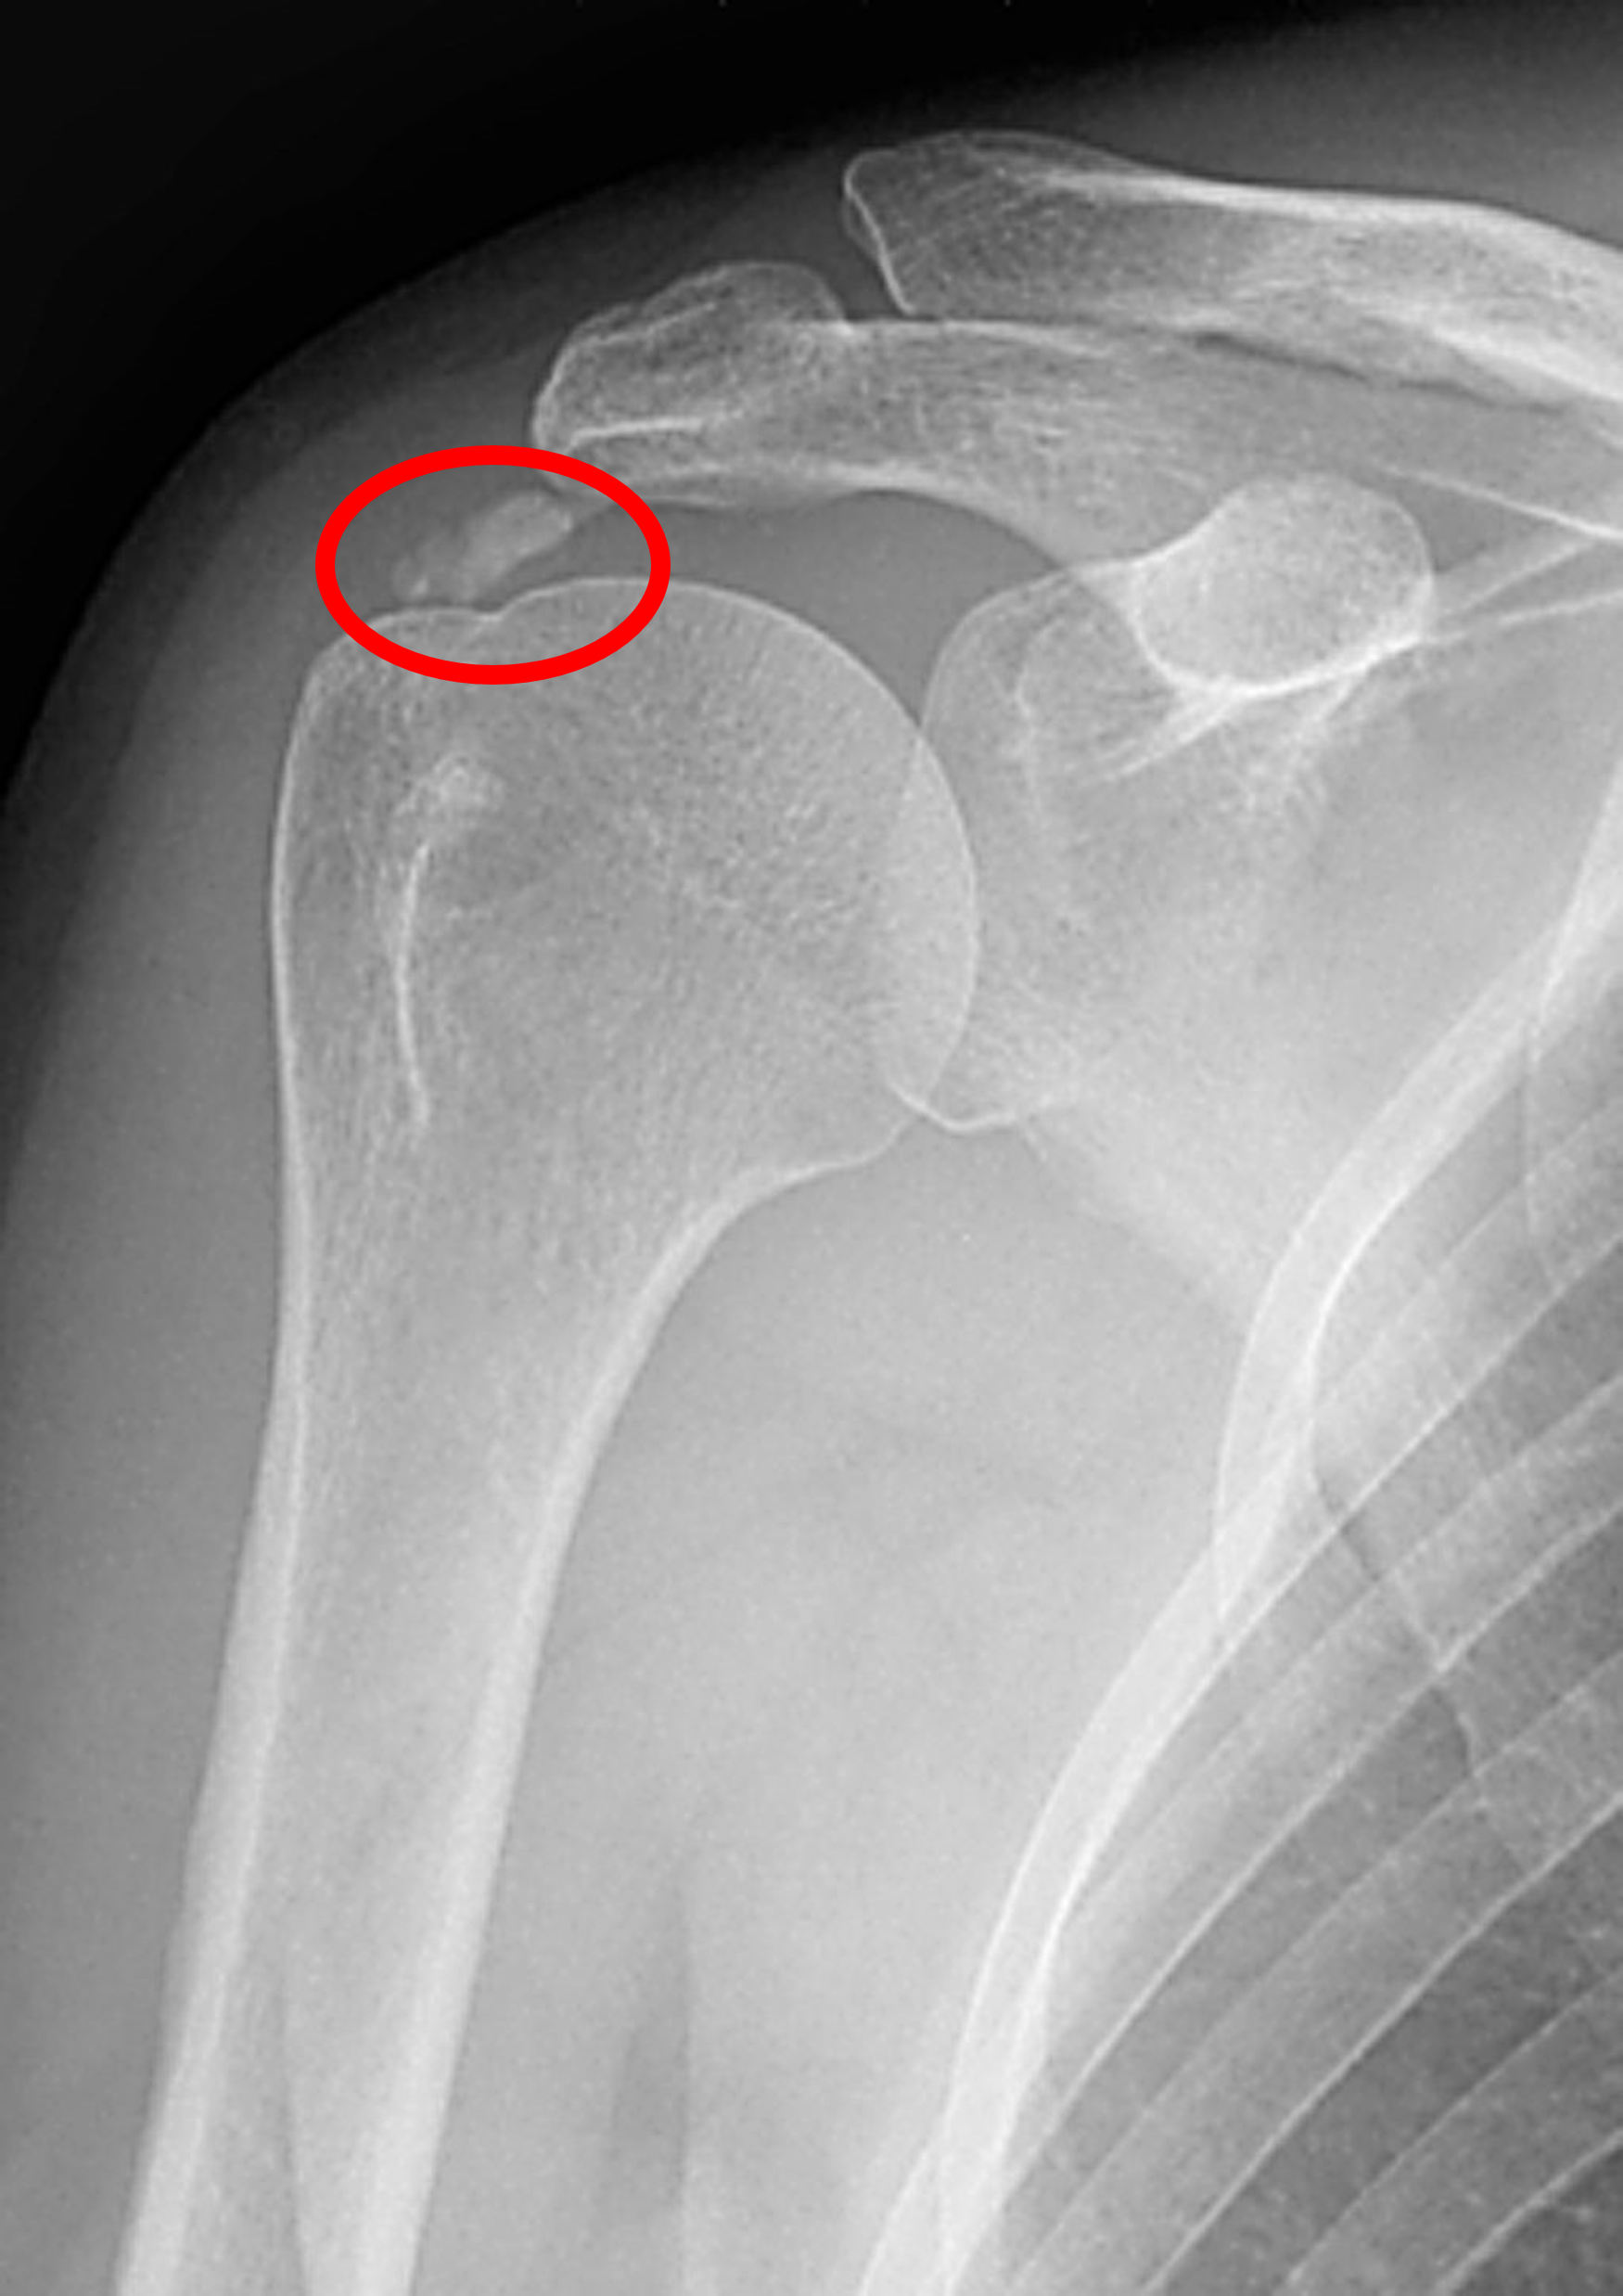

대부분의 석회성 건염의 환자에서, 석회가 형성된 이후 모든 시기에서 단순 X-ray 촬영만으로도 석회의 존재를 확인할 수 있게 됩니다. 대부분의 경우에는 회전근개가 상완골에 붙는 부착부위로부터 1-2cm 상방 부위에 석회 결정이 있는 것을 확인 할 수 있습니다. X-ray 영상상 석회가 명확하게 보일수록 더 질병이 진행되고 통증이 심할 것이라 생각하실 수 있습니다만, 실질적으로는 석회가 솜털같이 보이는 시기가 위에 말씀드린 연고와 같은 형태의 석회 물질을 이루는 용해기여서, 통증이 한층 더 심하다고 할 수 있습니다. 반면에 분필처럼 딱딱하게 경계가 명확하게 나타나는 석회가 발견되는 경우에 환자분들은 오히려 통증을 덜 호소하는 경우가 많습니다.

석회 침착물의 크기가 작거나 용해기처럼 솜털과같은 양상을 띄고 있는 경우에는, 단순 X-ray 촬영보다 초음파 영상을 통해서 진단하는 것이 더 쉽고 정확하게 진단할 수 있습니다. 또한 초음파의 경우 진단적 목적과 함께 병변을 실시간으로 보면서 병변 부위에 동시에 주사치료를 시행할 수 있어 각광받고 있습니다.